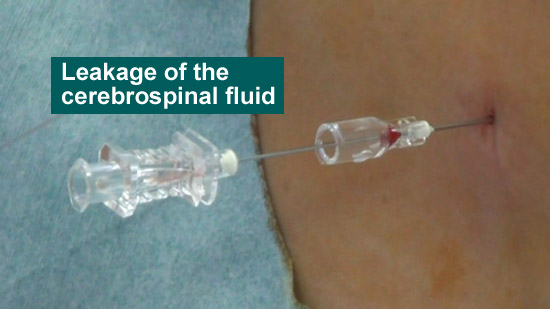

(5)Check the leakage of the cerebrospinal fluid

(6) Join an extension tube

Conduct the procedure with the extension tube hereafter